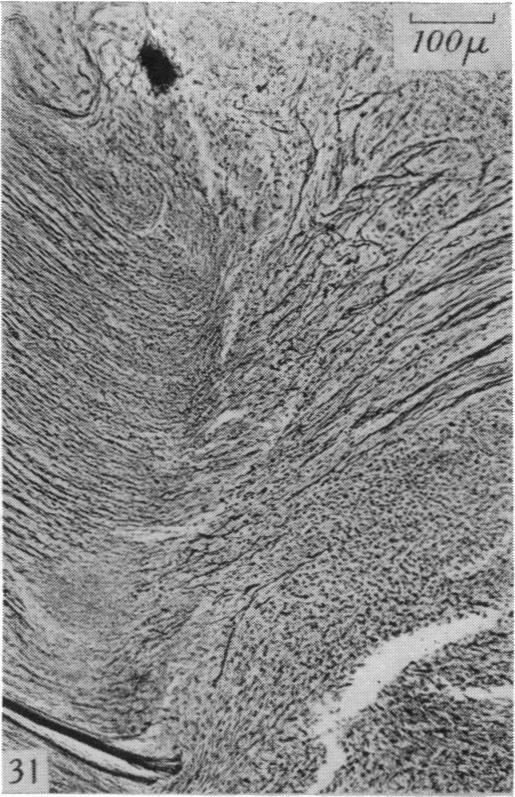

The degeneration and re-innervation of grafted nerves.

J Anat. 1942 Jan;76(Pt 2):143-166.7.